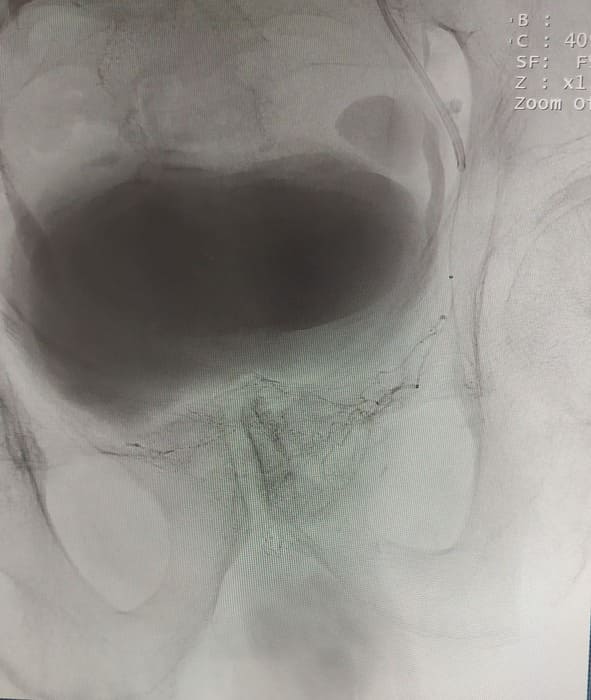

До нас звернувся пацієнт 79 р. Зі скаргами на періодичну затримку сечі. Скарги наростали поступово, на протязі кількох місяців. Особливістю даного випадку було те, що чоловіку в 2006 році вже було виконано через-міхурове видалення передміхурової залози. Проте частки що лишились дали ріст нової тканини. І за ці роки виросла нова патологічно збільшена залоза (майже 5см в діаметрі). Після дообстеження було виключено злоякісну природу цього утвору і ми вирішили перейти до операції.

Зазвичай люди літнього віку мають вражені атеросклерозом та звивисті, внаслідок гіпертонічної хвороби судини. Цей випадок не був виключенням, тому нам довелося докласти максимум зусиль, використати високотехнологічне обладнання та інструменти, щоб віднайти цільові судини. На диво, незважаючи на попередню операцію, судинний малюнок рецидивної простати збігався з тим який буває у не оперованих пацієнтів. Тому нам вдалося їх чітко визначити з обох сторін та заповнити емболами. Це доволі кропітка праця, адже щоб викликати ішемію, необхідно поступово виключити кровоплин в усій тканині залози. Полегшувало операцію лише відсутність перетоків артерій на сусідні органи. Це дозволило нам безпечно емболізувати, не боячись негативних наслідків та ускладненнь.

Операція була виконана 28.05.2021. під місцевою анестезією, доступом через прокол в правій стегновій артерії. Вже на протязі тижня зменшилась кількість походів в туалет по маленькому (вночі до 1 разу), полегшилось сечовиділення та покращилось самопочуття хворого.